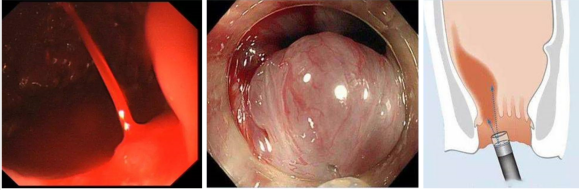

特色診療:擅長(cháng)診療各種消化系統疾病:包括食道、胃、大腸及肝膽脾胰各髒器器質(zhì)性功能(néng)性疾病。常規開展電(diàn)子胃鏡及結腸鏡檢查,膠囊内鏡檢查等。開展消化道出血内鏡下止血(藥物(wù)噴灑止血、電(diàn)凝止血、金屬钛夾止血);内痔出血的硬化治療,胃腸道息肉摘除術;空腸營養管置入術;内鏡下胃腸道早期腫瘤切除術(EMR);消化道早癌篩查,胃功能(néng)檢測,幽門螺旋杆菌抗體(tǐ)檢測及色素内鏡檢查;上消化道異物(wù)取出;碳呼氣實驗檢測HP(幽門螺杆菌)等。科(kē)室設備有(yǒu)奧林帕斯内窺鏡主機2台,胃腸鏡5條,膠囊内鏡設備,胃功能(néng)檢測儀等。